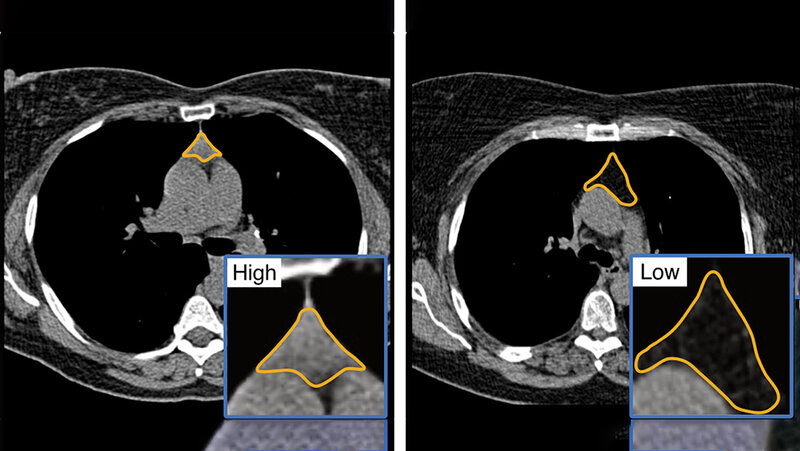

Mithilfe modernster Bildgebung in Form von computertomografischen Aufnahmen konnten die Forschenden zeigen, dass die Thymusdrüse sehr wohl eine Rolle für die Gesundheit spielt, insbesondere für gesundes Altern. Anhand des Grades der Verfettung kann damit die Gesundheit der Thymusdrüse eingeschätzt werden, eine Verfettung spricht dabei für eine bessere Immunfunktion. Der Thymuswert kann als Vorhersagewert für Überleben und Krankheitsrisiken verwendet werden. Mithilfe eines Deep-Learning-Frameworks konnten die Forschenden CT-Aufnahmen quantifizieren.